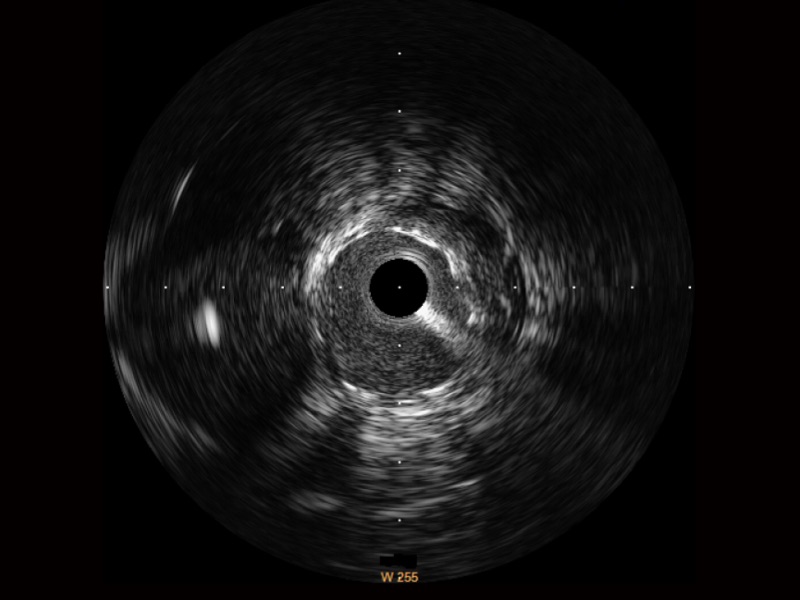

血管内超声(IVUS) 通过对病变程度、性质和累及范围的精确判断,可帮助选择治疗策略和方法,指导介入治疗过程,能够降低主要不良心血管事件,改善预后,在复杂病变介入治疗中用于指导支架置入的优势更为明显。血管内超声(IVUS)已成为精准心血管介入治疗的“金标准”。

新葡的京集团8814检测站始终关注未满足的临床需求:超宽频成像技术同时提供高清分辨力和充足穿透深度,适应不同血管结构的治疗引导;智慧赋能,简化操作,降低临床应用难度和缩短学习曲线。